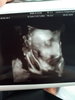

Jeszcze mam taką jakby języczek wystawiła ♥️♥️♥️

Załączniki

• 20180528_194321.jpg

20180528_194321.jpg

1,3 MB · Wyświetleń: 117